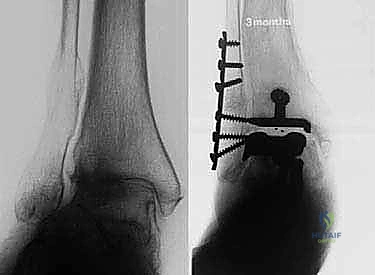

- الأشعة السينية (X-rays) بوضعية الوقوف: وهي الأداة الذهبية للتشخيص. صور الأشعة والوزن محمل على القدم (Weight-bearing X-rays) تظهر بدقة مدى تآكل الغضروف (ضيق المسافة المفصلية)، وجود نتوءات عظمية (Osteophytes)، وأي انحراف في المحور الميكانيكي للساق.

مفصل سالتو الأصلي هو ثمرة أبحاث أوروبية مكثفة. تم تطويره بين عامي 1994 و 1996، وبدأ استخدامه السريري بنجاح باهر في يناير 1997.

* التثبيت: هو مفصل "غير إسمنتي". يتم تغطية الأسطح المعدنية الملامسة للعظم بطبقة مسامية من التيتانيوم وهيدروكسي أباتيت (Hydroxyapatite). هذه الطبقة تشجع العظم الطبيعي للمريض على النمو داخل مسام المفصل (Bone Ingrowth)، مما يوفر تثبيتاً بيولوجياً صلباً يدوم لسنوات طويلة.

2. نظام سالتو تالاريس (Salto-Talaris Prosthesis - Fixed Bearing)

* التصميم الميكانيكي: يشارك هذا النظام نفس الهندسة التشريحية الممتازة للمكونات المعدنية لنظام سالتو، ولكن مع اختلاف جوهري واحد: المكون البلاستيكي (البولي إيثيلين) هنا ثابت (Fixed-bearing) ويتم قفله بإحكام داخل المكون المعدني العلوي (الظنبوبي).